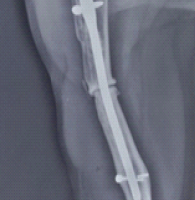

Reduction and fixation were confirmed clinically and fluoroscopically, followed by thorough irrigation and layered wound closure was performed and a sterile dressing was applied. Postoperatively, the limb was immobilized in a below-knee slab for 2 weeks, followed by a below-knee cast for an additional 4 weeks. The cast was removed at 6 weeks. Subsequently, ankle and subtalar range-of-motion exercises were initiated, along with toe-touch weight bearing, gradually progressing to full weight bearing by 8 weeks. At 1 year, follow-up radiographs confirmed satisfactory implant position with good progression toward complete bony union (Fig. 5). Clinically, the patient was asymptomatic and demonstrated full, pain-free ankle range of motion at 1 year review (Fig. 6).

Figure 5: Anteroposterior and lateral ankle radiographs at 1-year follow-up showing complete radiological union with maintained alignment.